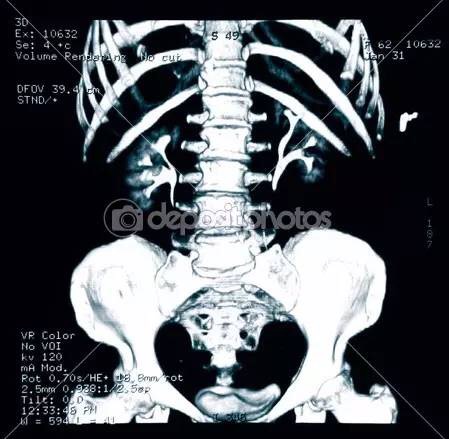

根据美国放射协会和妇产协会的数据,孕妇接受单次胸部x线检查腹中胎儿受到的照射剂量为0.02–0.07毫rad。记住,高于5000毫rad才会造成胎儿损伤。单次腹部x线平片胎儿受到的照射量为100毫rad,肾盂静脉造影胎儿受到的照射量可能大于1rad。乳腺钼靶检查胎儿受到的照射量为7-20毫rad。钡灌肠或者小肠连续成像检查胎儿受到的照射量可以达到2-4rad。头胸部CT检查胎儿受到的照射量小于1rad。腹部或者腰椎CT扫描胎儿受到的照射可以达到3.5rad。

也就是说,普通x线平片通常只会暴露胎儿于非常小的照射剂量。而且通常孕期需要做x线检查时候,孕妇的腹部是会用含有铅的防护衣保护起来的,更进一步降低受照剂量。除开钡灌肠和小肠连续成像,绝大多数造影剂荧光检查也只会给胎儿带来毫rad的剂量。CT造成的照射依照射数量和成片距离会有不同。盆腔CT可能会给胎儿带来高达1.5rad的照射,但放射科医生通过使用低剂量技能是可以将它降低到接近250毫rad的。